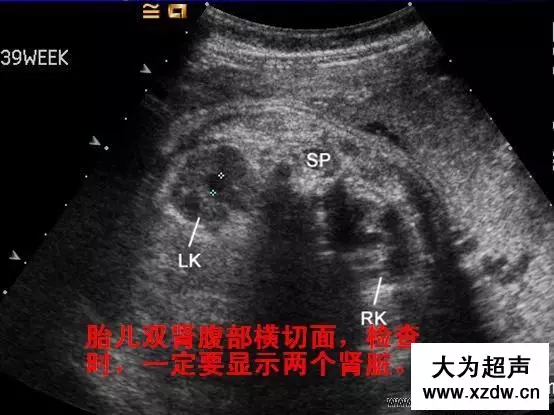

產科超聲正常圖片